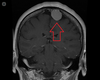

Quais os sinais de alarme que sugerem a possibilidade de Cefaleia Secundária e necessitam de exames complementares?

- Sinais neurológicos focais, alteração consciência, convulsão.

- Características progressivas (lesão expansiva?).

- Pacientes com neoplasia ou HIV.

- História de queda ou TCE recente.

- Edema de papila.